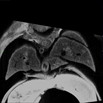

Caption Play MovieSerial 2D EFIC image stack in the coronal plane of 2349-002-LA (E15.5) shows mirror image dextrocardia and mLV hypertrophy